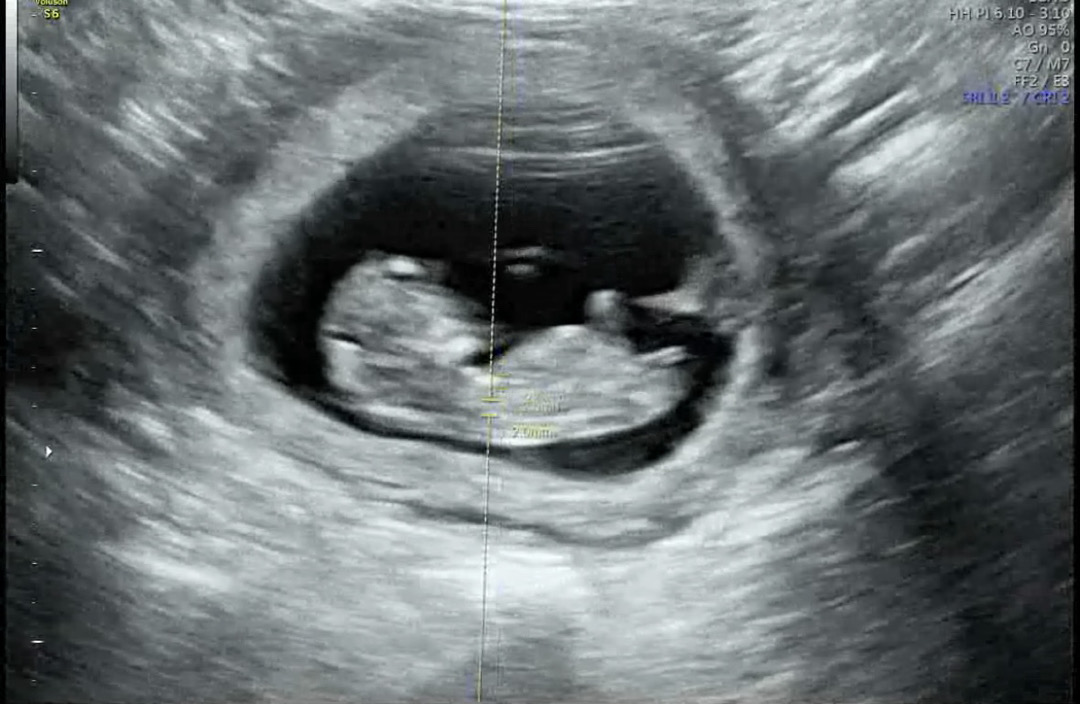

각도법 성별 궁금해요 🥹

여기 초음파 화질이 안 좋은 편이지만 캡쳐 잘돼서 올려봅니다

딸 같아요!

아가가 아직 작아서 성별을 모르겠어요ㅠㅎㅎ..